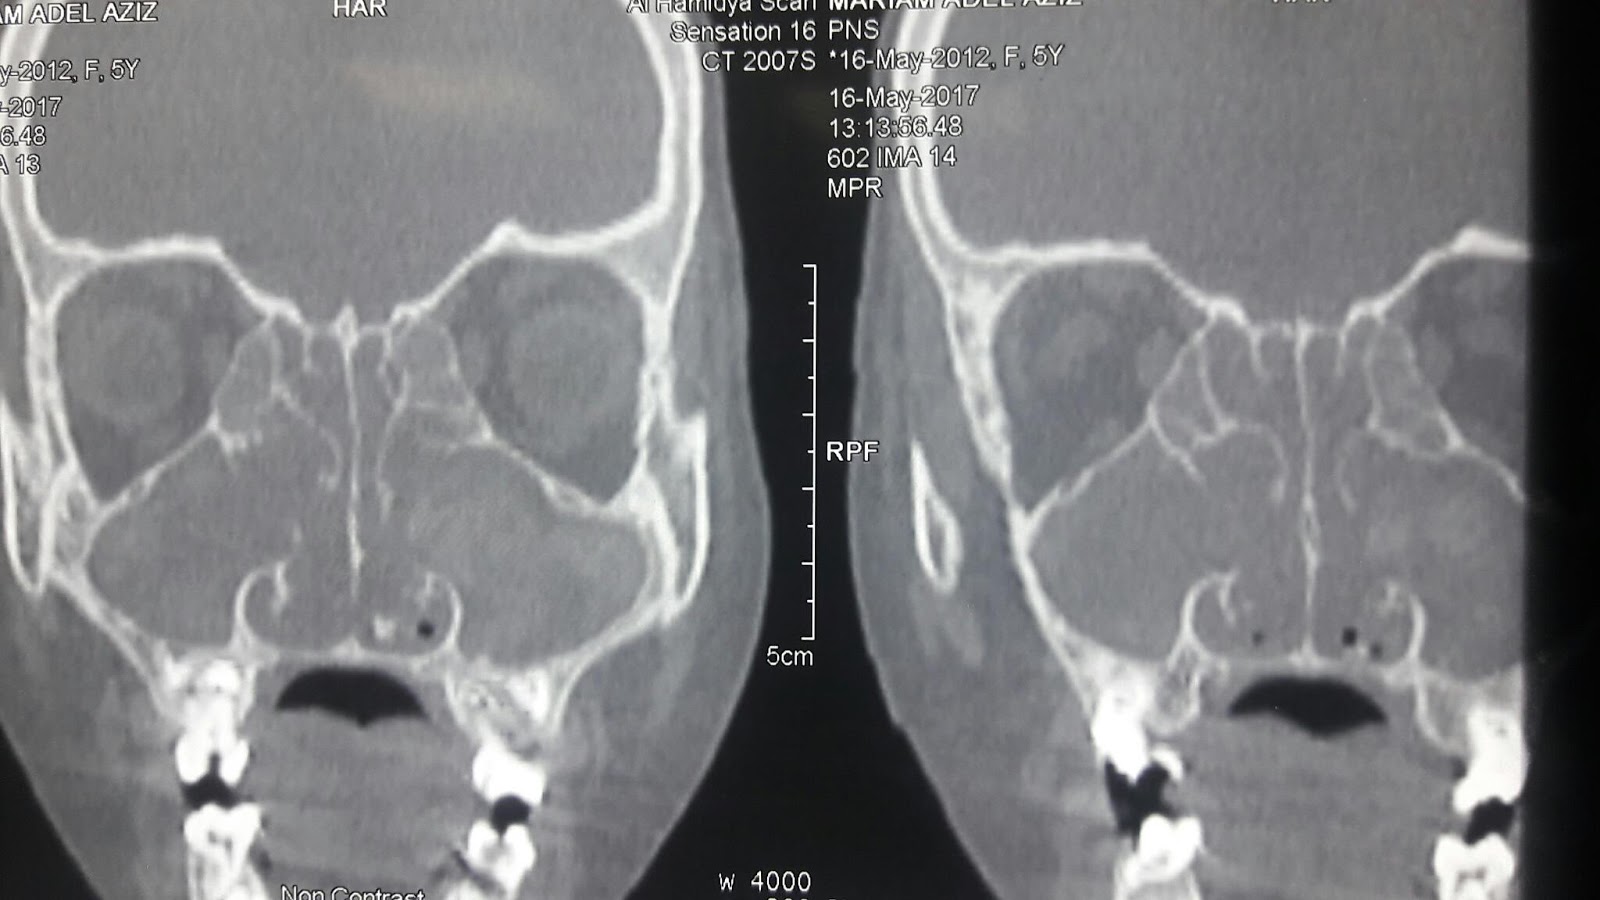

CT scan nasal and paranasal sinuses axial, coronal and saggital cutts showed bilateral soft tissue density on both side of the nasal cavity and occupying anterior, posterior ethmoid and maxillary sinuses.

This density is heterogenous and contains hyperdense foci giving motteled appearance most probably due to fungus infection.

This hyperdense foci due to minerals produced by the fungus like magnesium and iron. There is also bone remodling of the sinuses. Other laboratory investigation done like taking biopy from the nasal mass for fungal stain and culture which reveal septate hyphea with 45 degree angle septation. The fungus was aspergillus. Ige specific to the fungus detected in blood, which confirm diagnosis of allergic fungal rhinosinusitis. Other laboratoy investigation to prepare the patient to the nasal sinus surgery. Allergic fungal rhinosinusitis may be a part of allergic pulmonary aspergellosis. So we have to look at the chest to exclude this entity.